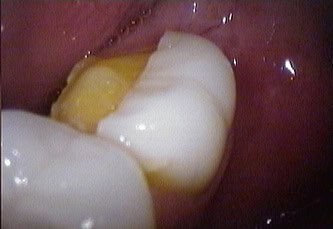

Chipped crown due to heavy bite, and clenching, was repaired in one visit, using OA1 composite was used to repair the porcelain crown.

Emax crown fractured due to heavy bite, although Emax is one of the strongest porcelain, chip, and fracture can happen if the patient does not wear night guard or bite splint.

Porcelain Repair in LA can be done in one visit. Dental bonding repair works best toward the gum, rather than the incisal edge of the tooth. The edge or tearing the surface of tooth porcelain is not strong and can fracture again. Porcelain repair at the edge or corner of chipped porcelain is very temporary.

Dental composite bonding can be used to repair the broken piece and put in the right occlusion, Ideally is best to get a new Emax crown vs repairing a broken crown.